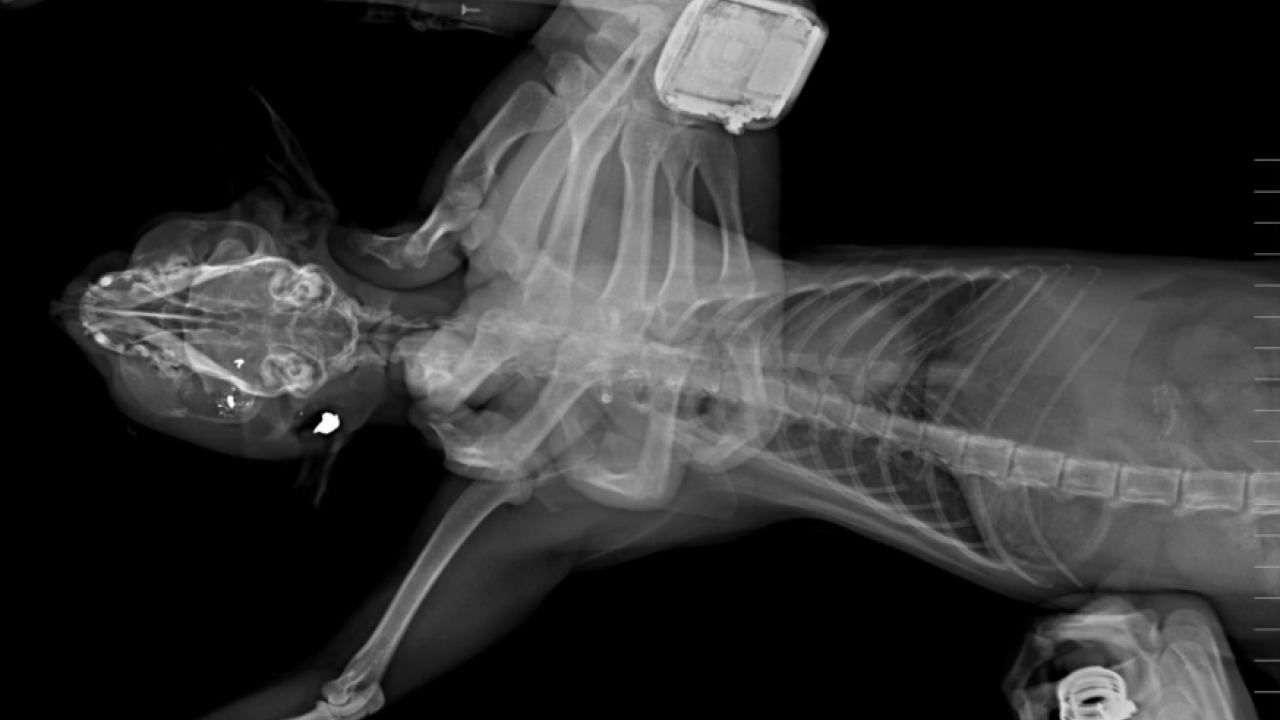

Edirne'nin İpsala ilçesinde hayvansever Hüseyin Bülbül (42) tarafından bakılan kedilerin av tüfeği ile vurularak öldürülmesine ilişkin komşusu K.G. (56) hakkında 6 aydan 3 yıla kadar hapis cezası istemiyle dava açıldı. İpsala ilçesine bağlı Köprü Mahallesi'nde 2018 yılından bu yana devam eden kedi ölümlerine ilişkin hayvansever Hüseyin Bülbül, olayın peşine düştü. Bülbül, son 7 yılda beslediği kedilerin bazılarının ortadan kaybolması, bazılarının ölü bulunmasının ardından sokağın belirli noktalarına güvenlik kamerası yerleştirdi. Hüseyin Bülbül ayrıca ölü bulunan kedileri özel bir kliniğe götürdü. Klinik raporunda, 'ateşli silah yaralanması ile uyumlu patolojiler' tespit edildiği, hayvanların tüfek saçması sonucu öldüğüne ilişkin bulgulara yer verildi. Bülbül, güvenlik kamerası görüntülerinden komşusu K.G.'den şüphelendi. Görüntülerde; K.G.'nin bahçesine giren bazı kedilerin aniden kaçtığını fark etti.

KOMŞUSUNDAN ŞİKAYETÇİ OLDU Hüseyin Bülbül, komşusu K.G.'den şikayetçi oldu. Eve giden İpsala İlçe Emniyet Müdürlüğü ekipleri, K.G.'ye ait ruhsatlı 2 av tüfeğine incelenmek üzere el koydu. Öte yandan K.G.'den alınan svap örneklerinde sol elinde atış artıklarına rastlandı. K.G., emniyetteki işlemlerinin ardından adliyeye sevk edildi. Savcılık ifadesinde suçlamaları kabul etmeyen K.G., yurt dışına çıkış yasağı konularak adli kontrol şartıyla serbest bırakıldı. 'YETERLİ ŞÜPHE OLUŞTURACAK DELİL MEVCUT' İpsala Cumhuriyet Başsavcılığı'nın olaya ilişkin hazırladığı iddianamede K.G., hakkında, 'Bir ev hayvanını veya evcil hayvanı kasten öldürme' suçundan 6 aydan 3 yıla kadar hapis cezası istendi. İddianamede, "Herhangi bir silah ateşleme görüntüsü tespit edilmese de şüphelinin ikamet ettiği evin bahçe kapısı önünde bir kedinin can çekiştiği ve bir kedinin de kaçtığının tespit edildiği, dosya kapsamında tanık olarak beyanı alınan S.Ç.'nin şüphelinin bahçe kapısı önünde bir kediyi yatar vaziyette gördüğünü, başını sevmek istediğinde kedinin ölü olduğunu fark ettiğini, kediyi eline aldığında başından kan aktığını görmesi üzerine yol üzerinde kalmaması amacıyla kediyi çöp tenekesinin içerisine bıraktığını, ölen ve yaralanan 2 kedi hakkında düzenlenen 25/08/2025 tarihli veteriner hekim ön muayene raporu ile çekilen radyografilerde ateşli silah yaralanması (kuş saçması) ile uyumlu patolojiler gözlemlendiği şeklinde rapor tanzim edildi. Tüm dosya kapsamı incelenmekle şüpheli savunması, bilgi sahibi beyanları, İpsala İlçe Tarım Müdürlüğü'nün yazılı başvurusu, müşteki beyanı, kamera görüntüleri ve kriminal raporları birlikte değerlendirildiğinde, şüphelinin olay tarihinde müşteki Hüseyin Bülbül tarafından da beslenmekte olan sokak kedilerine ateş etmek suretiyle, bir kedinin ölümüne neden olarak üzerine atılı suçu işlediğine dair ve bir kedinin yaralanmasına neden olarak tariflenen suçu işlediğine dair hakkında kamu davası açmak üzere yeterli şüphe oluşturacak kadar delilin mevcut olduğu anlaşılmakla" denildi.